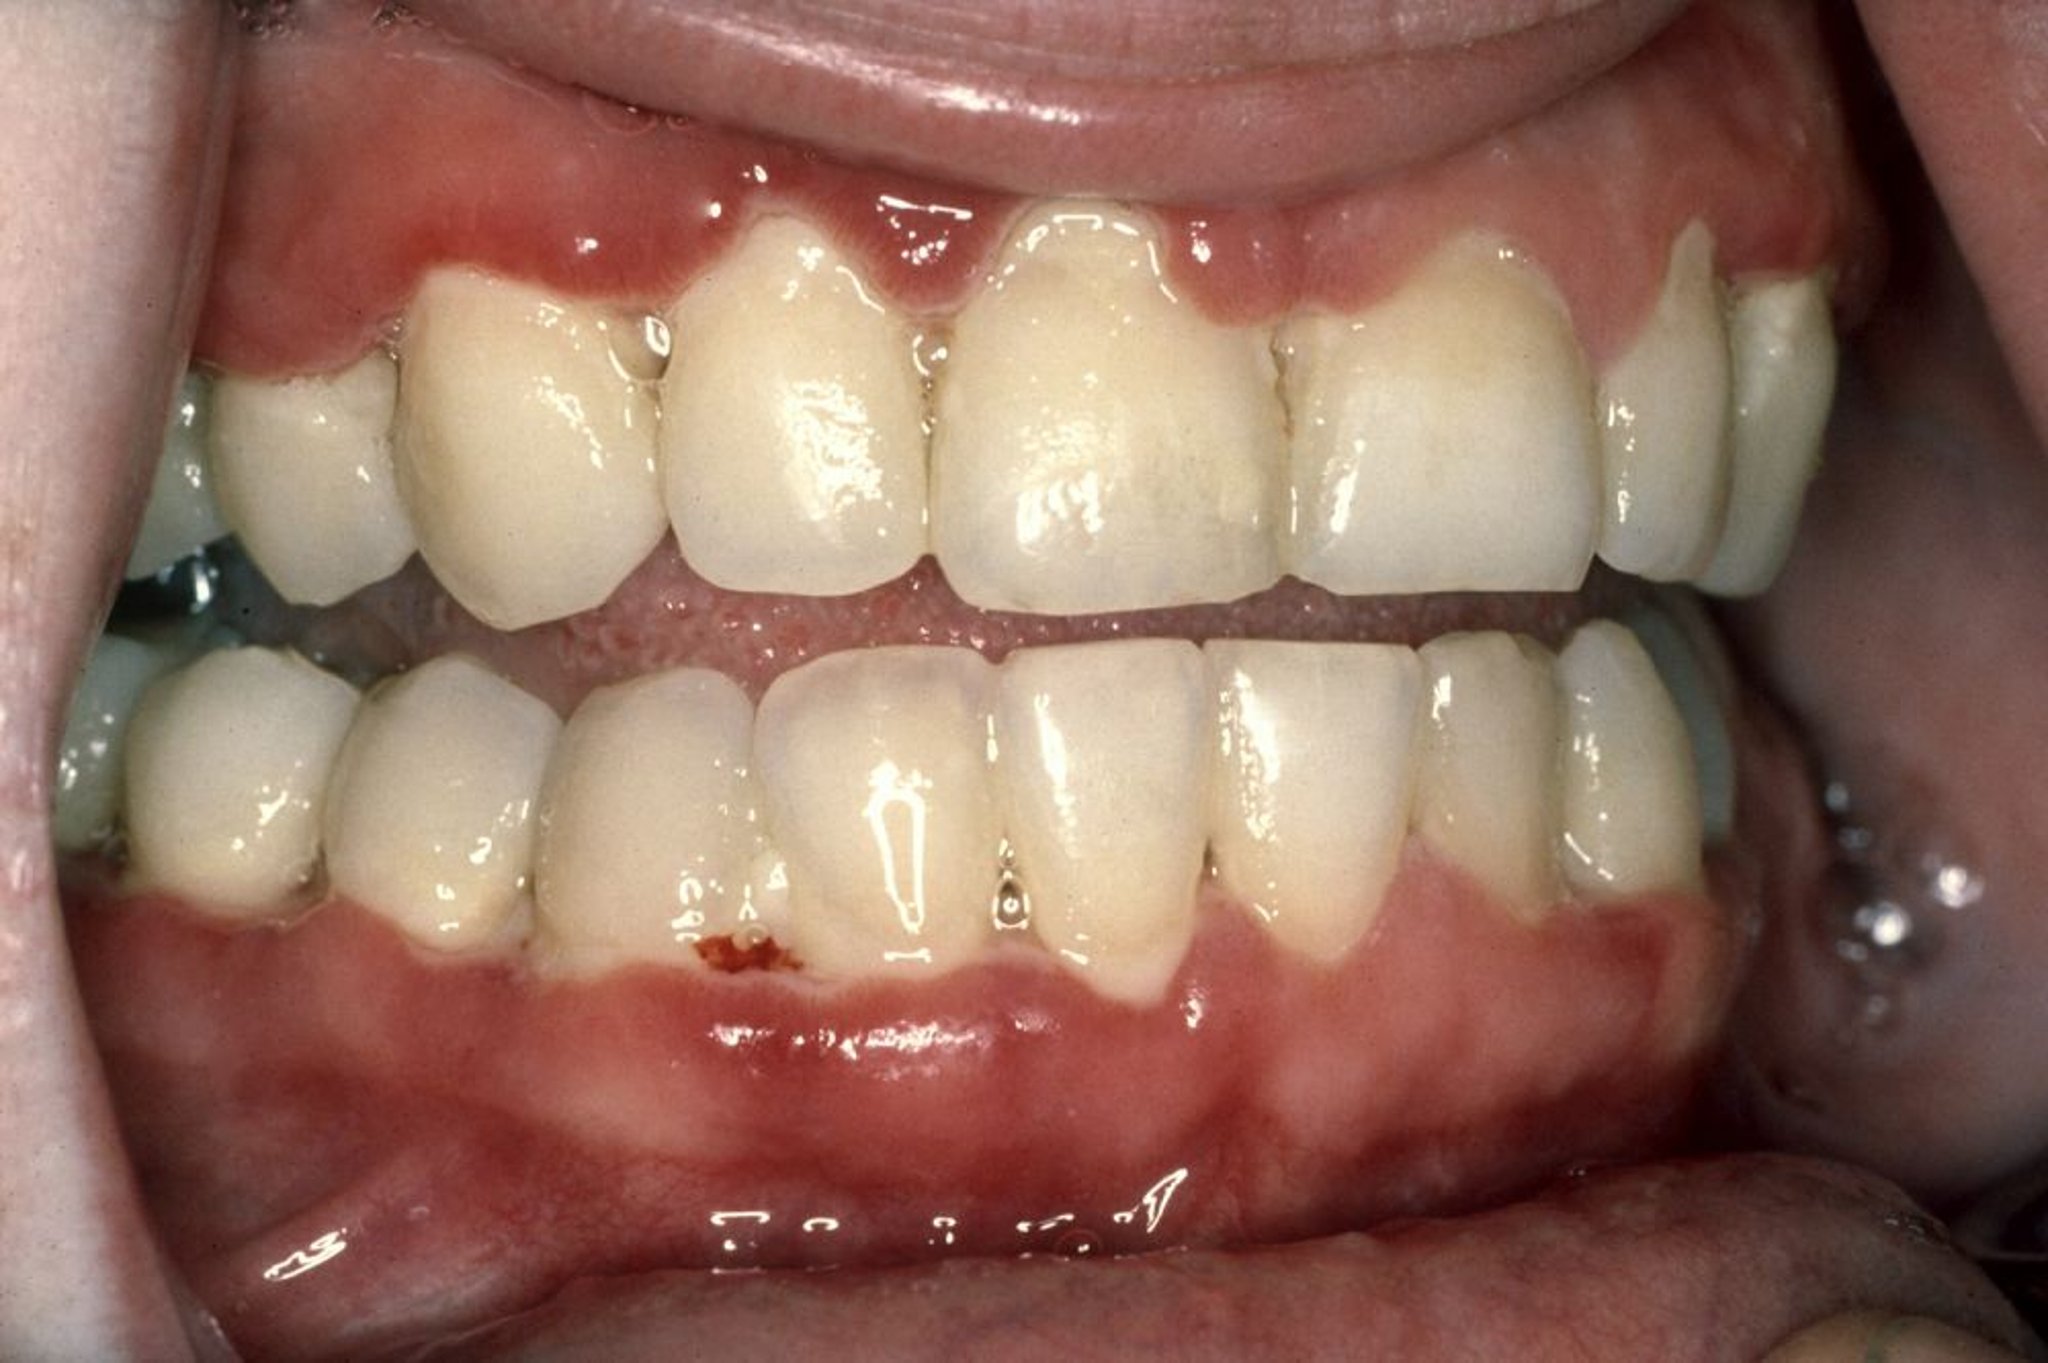

एक्यूट नेक्रोटाइज़िंग अल्सरेटिव जिंजिवाइटिस (ANUG) की पहचान मसूड़ों में दर्द उठने से की जाती है जिनमें आसानी से खून बहता है, दांतों के बीच का गम टिशू घटने लगता है और खत्म हो जाता है, और साँस में बदबू जैसे लक्षण दिखते हैं। इस तस्वीर में, एक बहुत लाल गम टिशू को दिखाया गया है। मुँह के निचले भाग के आगे की मसूड़ों की परत पर साफ़ देखा जाता है, वहां पर एक सलेटी, मृत ऊतक (स्यूडोमेम्ब्रेन) की एक पतली से कतार भी होती है जिसमें आसानी से खून बहता है।

इमेज क्रेग फाउलर, DDS के सौजन्य से।